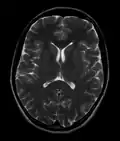

This axial T2-weighted (CSF white) MR scan shows a normal brain at the level of the lateral ventricles.